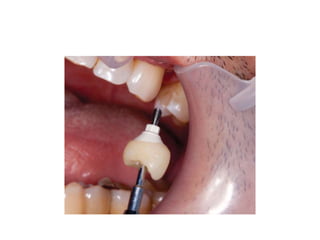

Fixed implant supported restorations

Screw retained Cement retained